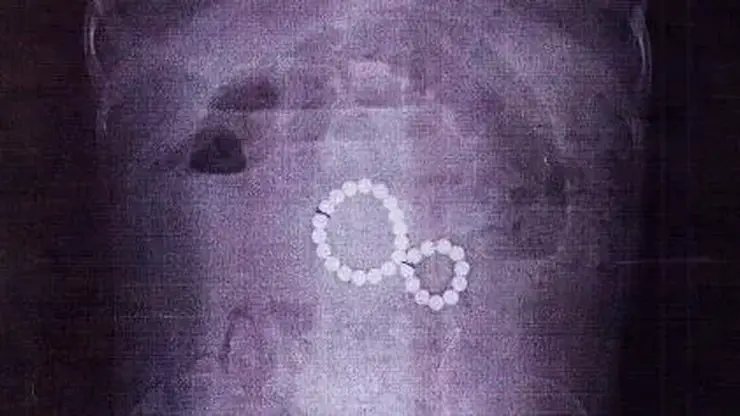

Первоначально в поликлинике по месту жительства у девочки подозревали энтеровирусную инфекцию. Однако, из-за сильных болей и рвоты с кровью, врачи назначили рентген. Снимок показал скопление магнитов, слипшихся в «восьмёрку», что привело к повреждению кишечника.